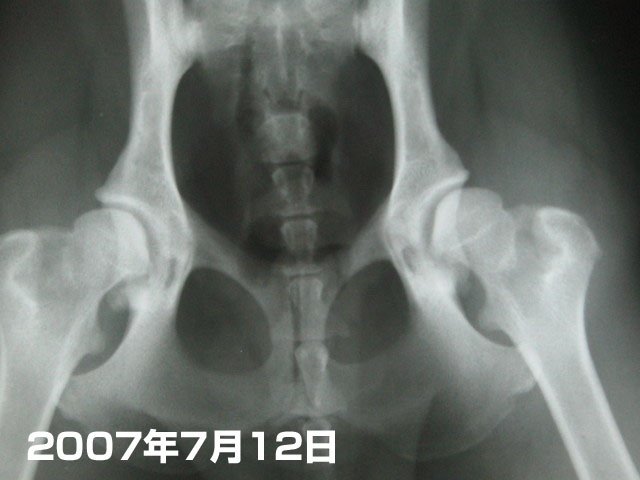

で、これは本日。

どうだいp(`ー´)q かなり良くなってるでちょ〜〜!!!!!!!\(^ω^\)( /^ω^)/

成長期だから、これから良くなる可能性もあるって先生がおっしゃってたけど....ママは内心、悪くなることはあっても良くなることはないんじゃないのぉ〜(´ヘ`;)......って実は思っていたの。

でもそれははずれたね〜(^-^)v

まっ、4枚目も5枚目も麻酔をかけて撮った物じゃないのでガッチリ正確ではないかもしれないけど、様子をみるには十分ね。

成長して少し筋肉がついてきたからかな?

やっぱり水泳はいいのかな〜♪

歩き方とかは悪い時とたいしてかわらないと思うけど、まっ、この調子でいてくれたら良くないながらも普通の生活に支障はなしね(^-^)v

こちらも気張りすぎないで、気をつけいていてあげようっと(^.^)

【後日談】7月26日に定期健診に行った。

もいたんの股関節が悪いとわかってから、先生のすすめでもいたんにもベターシャークをあげているんだけど、先生はベターシャークも功を奏しているのだろうとの事。この調子でいけば、わりときれいに股関節が形成されるかも★('-^v)

(本当は股関節疾患の成長期にはあげないほうがいいらしいけど、もいたんにはOKみたい(^^ゞ)